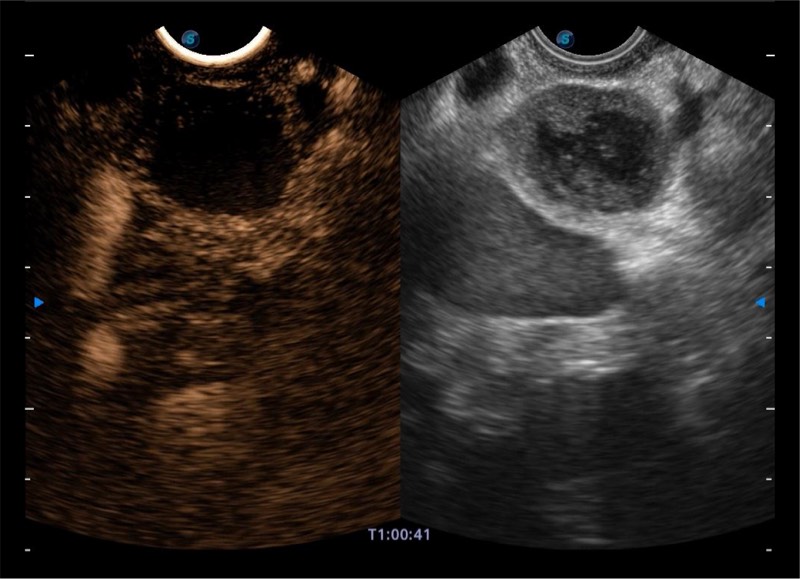

搭载百万级CMOS成像技术

及自主研发凸阵换能器,

可呈现优质的内镜和超声画面

基于二十年的超声技术积累,球速体育入口提供了最新一代的独立超声主机,在提供高质量图像的同时满足多学科使用。具备常见多普勒技术并提供弹性成像、声学造影等高端影像技术。新一代传感器具有更强的抗干扰能力并减少图像伪影。

4-12MHZ宽频输出